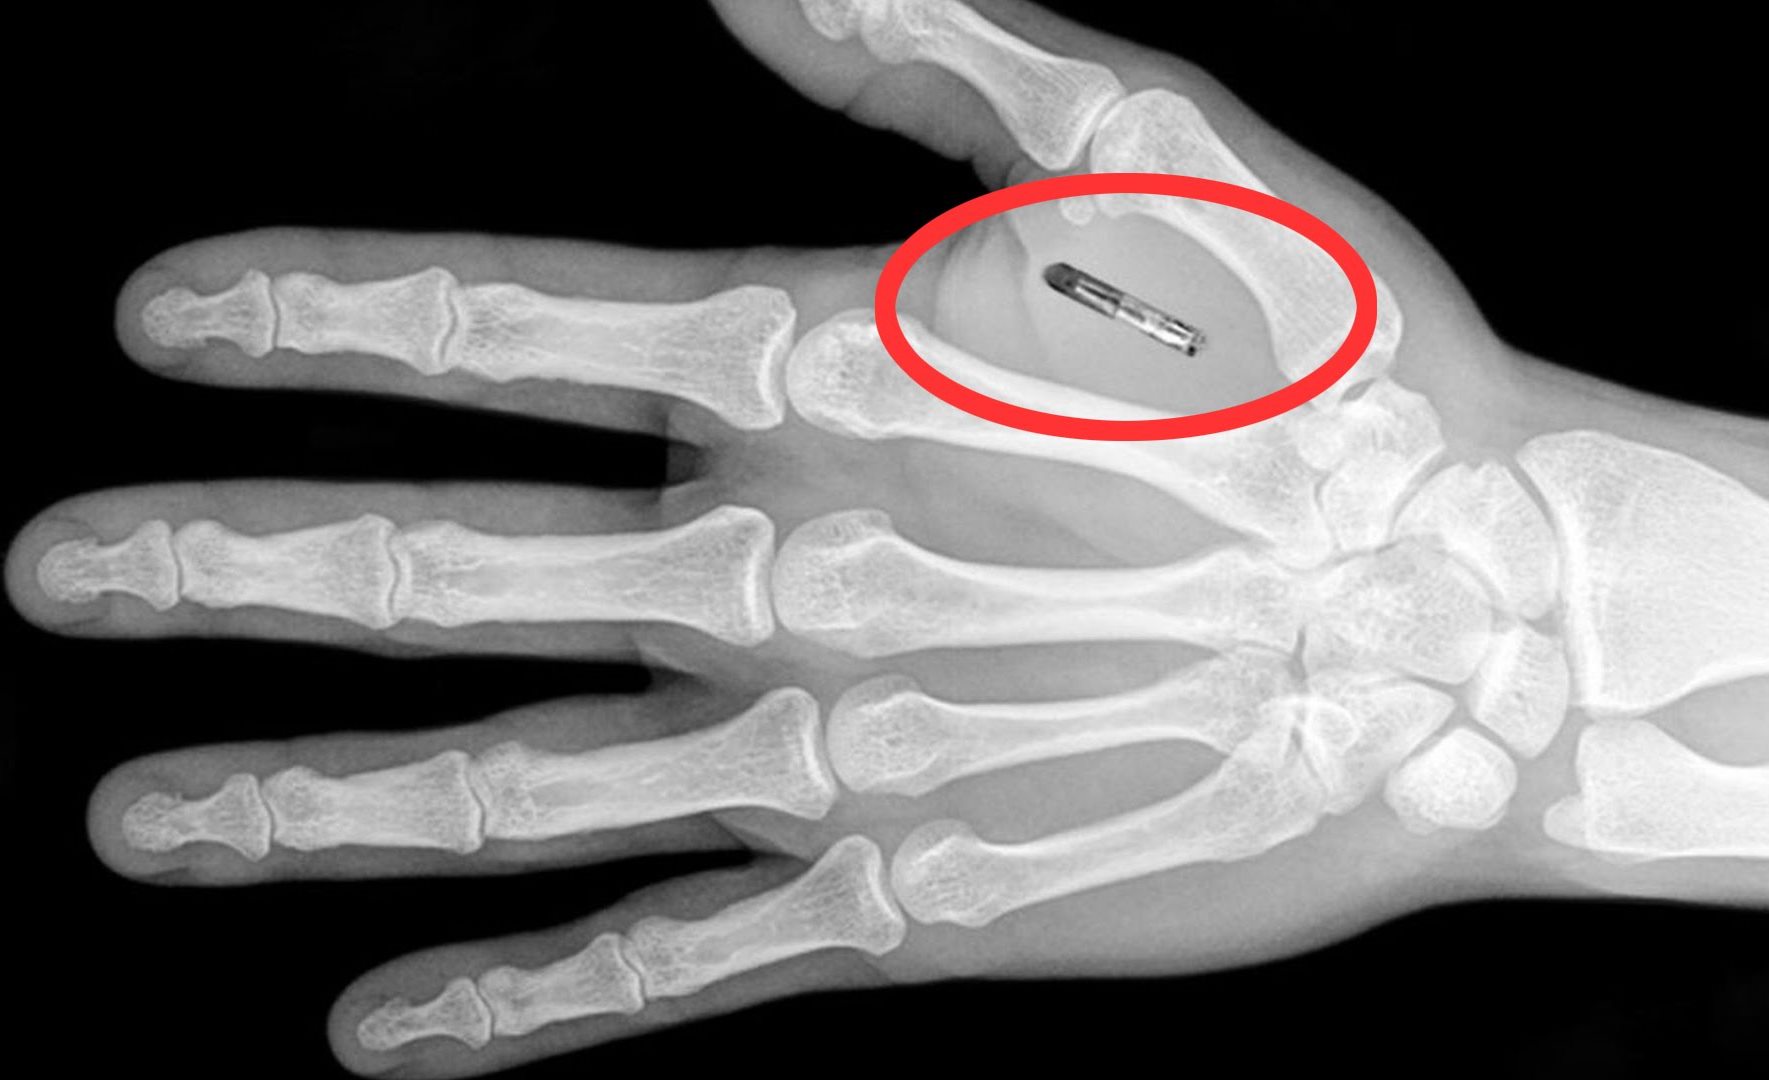

Američka tvrtka Three Square Market iz Wisconsina odlučila je napraviti jedan mali korak u tom smjeru, pa je svojim zaposlenicima ponudila mogućnost da im ugradi mikročip implantate, za koje je napisala softver koji omogućuje da otključavaju vrata bez ključeva, logiraju se na računala te kupuju hranu i piće na automatima i u kantini tvrtke bez novca.